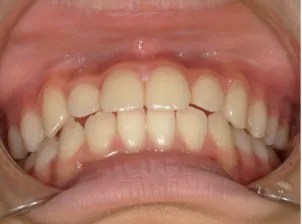

治療前①小2:8y1m 初診

| カウンセリング・診断結果 | 前歯が受け口になっていているため、適正な成長へ誘導するために前歯の咬み合わせの改善が必要なことを説明し、診断を希望されたので精密検査へ進みました。 精密検査の結果、骨格的には受け口傾向、下顎前歯の突出、上下ともアーチが小さく凸凹(叢生)が認められ、機能的には低位舌と口唇閉鎖不全があり、口元は上下唇とも突出していますがコンケーブになってないことがわかりました。 |